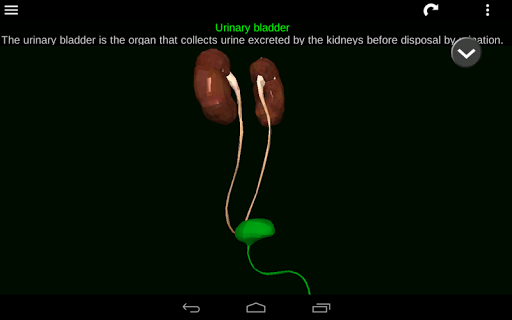

* Sistem pencernaan, termasuk lambung, usus kecil, usus besar, dan animasi sistem ini.